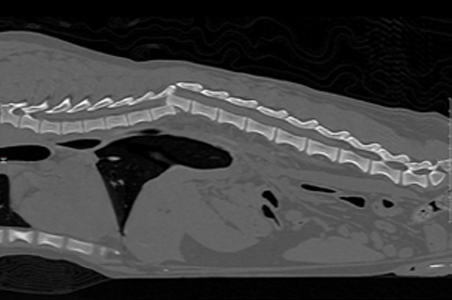

CT 검사를 통해 일반적인 방사선 상에서 확인할 수 없는 3차원적인 volumetric image를 구현하여 mm 단위의 작은 병변에 대한 감별과 정교한 3D 영상을 통해 선천적인 장기 또는 혈관 기형, 종양 및 전이 평가, 근골격계 질환, 비강/두개골 질환 등 다양한 질환의 진단에 사용될 수 있습니다.

근골격계 CT

선천적 기형, 발달상의 근골격계 질환, 근골격계 종양, 퇴행성 관절염 등